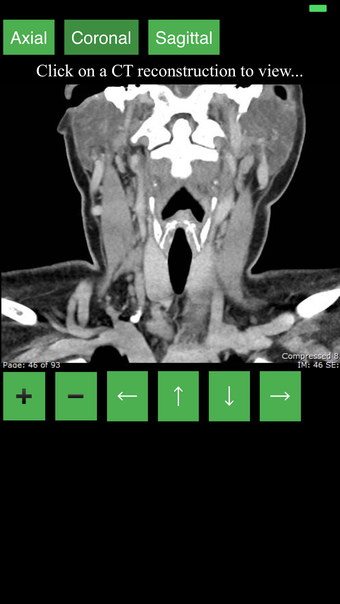

Ta aplikacja jest najwygodniejszym sposobem na przeglądanie i badanie przekrojowo anatomii człowieka na skanie CT. Może być używana jako materiał referencyjny i narzędzie edukacyjne.

Aplikacja wyświetla przekrojowy obraz tomograficzny ciała człowieka i używa systemu kodowania kolorów, aby łatwo identyfikować różne struktury tkanek miękkich i kości. Może również być używana do badania określonej części ciała, takiej jak szyja, czaszka, obręcz barkowa lub klatka piersiowa.

Użytkownik może przesuwać obraz i powiększać go, aby lepiej zidentyfikować struktury i powiększyć obraz do dalszych badań.